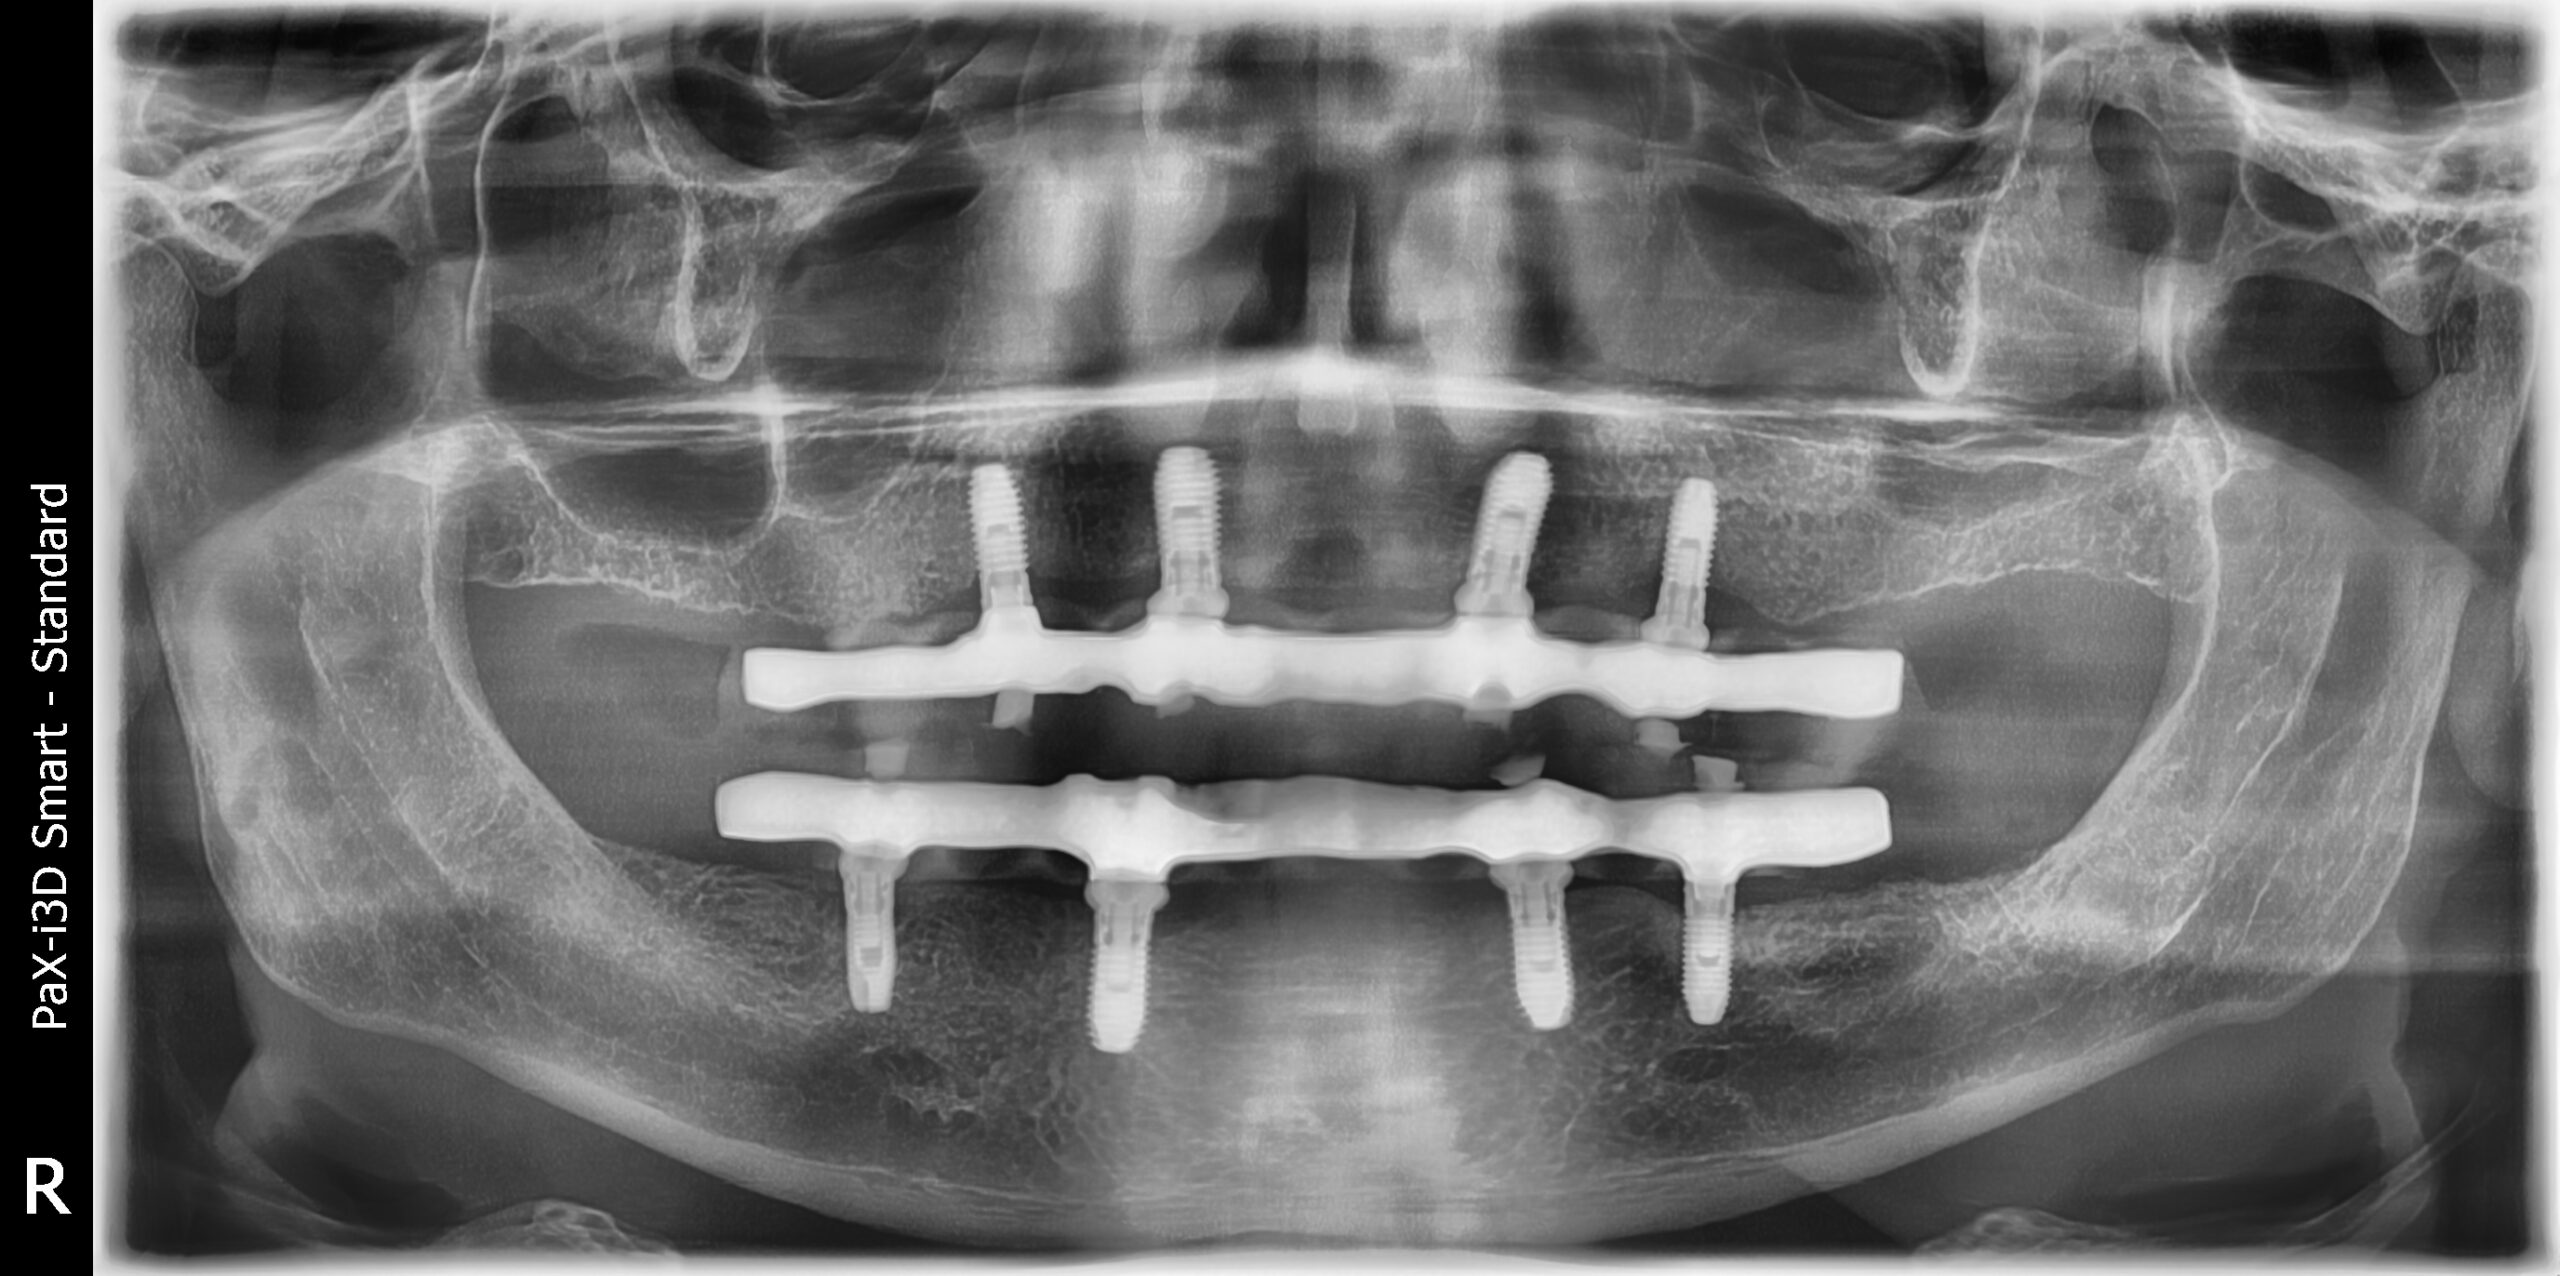

Insieme al paziente abbiamo deciso che la soluzione migliore fosse una riabilitazione totale delle due arcate con la rimozione dei denti residui e l’inserimento di 4 impianti nell’arcata superiore e 4 impianti nell’arcata inferiore, sui quali sarebbero state poi avvitate le protesi fisse (All on four).

Questa soluzione prende il nome di “Toronto Bridge” e prevede la realizzazione di protesi complete di tutti denti, avviate agli impianti. Tale soluzione, quando clinicamente possibile, permette una rapida e definitiva risoluzione dei problemi estetici e funzionali.